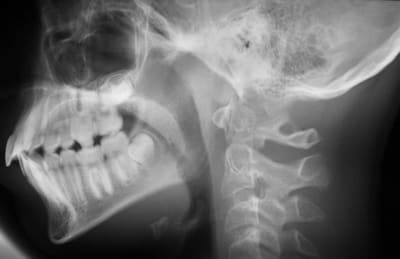

N’étant pas du tout un « pro » de l’interprétation des mesures céphalométriques, pourriez-vous m’indiquer TOUT ce que me cachent ces quatre images :

Il s'agit d'un analyse de DOWNS ou on prend comme référence des plans qui sont doubles, et qui demandent une interprétation.

Ceci dit, on voit un déplacement de l'incisive Sup; associé a la lèvre Sup.

Mais on voit aussi à 13 ans une proximité de la tète du condyle avec le conduit auditif qui, s'il ne s'agit pas d'un erreur de tracé doit donner de grandes, d'énormes, douleurs condyliennes.

Tu es devant une Cl. III. sans doute par un hypodéveloppement du Max. Sup. Comme on n'est pas en grandeur réelle je ne peux faire que des proportions. Celle de 5/6 entre la base du crane Po/Na et Xi/Pm n'est pas respectée.

Ou le Max. est trop petit, ou la Md. est trop grande, ou les deux à la fois.

D'autre part tu es en bout à bout cuspidien. Cl. 0.5. Ce qui est tres défavorable. C'est la pire des occlusions. Avec une version des incisives Sup. éxagérée.

Il est vrai qu'a vue de nez, les molaires sont en classe 2 angle en debut de traitement avec un big ANB au debut, qui s'est bien réduit comme le souligne catrose

Une proalveolie sup de suceur de pouce , bien réduite 3 ans aprés.

L'ANB s'est surtout réduit..parce que le patient ferme la bouche sur la deuxieme radio! -donc le point B "avance" et l'angle se réduit). La premiere radio n'est vraiment pas exploitable, l'inocclusion est complète.

La proalvélie sup s'est LEGEREMENT réduite (prendre comme référence l'angle entre l'incisive sup et le plan palatin), tout comme la proalvéolie inf s'est légèrement accentuée (voir par rapport au plan mandibulaire): c'est simplement une compensation dento-alveolaire de la cl.II squelettique, les incisives "cherchant" un contact.

Il n'existe, à priori, pas de signes radiologiques évidents pour affirmer que cette CLASSE II BIPRO (mais oui, Bjc!!!) soit celle d'un suceur de pouce car:

-reduction de ANB par recul du point A(par rapport au Nasion)

-l'occlusion de la premiere photo est incomplete evidemment car c'est un cas d'interposition de la langue en position d'occlusion de repos(je n'invente rien,je lis"conscious occlusion"), cas de deglutition infantile avec beance anterieure

-moi j'ai mesure ANB= 4.5,ce qui est une classe 1 acceptable?

-oui a la compensation dentoalveolaire des incisives qui se touchent enfin

Ok, le point A semble avoir légèrement reculé (les tracés sont-ils fiables?), mais je mesure un ANB de 5,5, valeur d'une cl.II légère, qui correspond d'ailleurs à une cl.II dentaire assez discrète également (apparemment 1/2 cuspide).

Cette apparente Cl. II. en bout à bout n'est pas du à une succion du pouce mais une longueur accentuée de la branche horizontale de la Md.

( 85 au lieu de 72 mm. à cet age)

C'est l'un des cas ou la céphalo. est la plus utile. Vous avez une seule mesure de longueur sur le tableau, mais avec celà, vous pouvez mesurer quand mème 3 signes d'alerte de Cl. III. squelettique.

dans ce cas je vois aussi une vestibuloversion importante des incisives inferieures ,un ANB tres positif ,un point A tres en avant de la projection Nasion sur Francfort,une difference Co-A - Co-Gn normale,bref on baigne dans la classe I voire II squelettique.

Donc j'ai du mal a switcher sur une prevision de croissance classe III

Il y a donc perturbation de la valeur dela longueur de la branche horizontale (tu as mesure 85 sur la derniere tele?)?